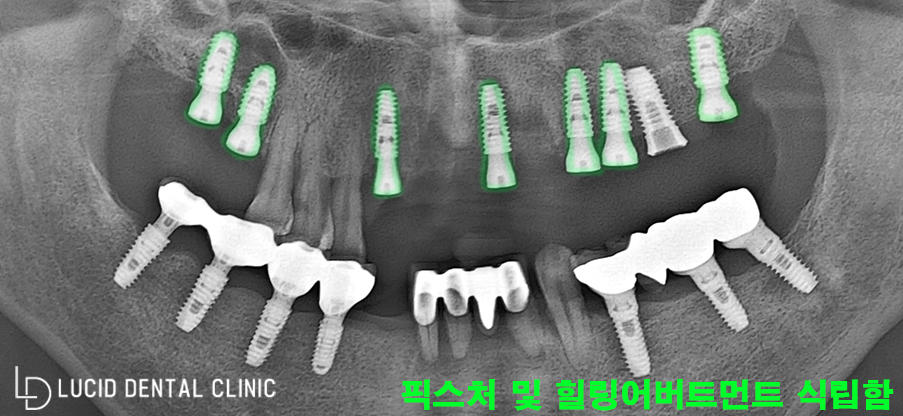

파노라마를 찍어 확인하니

이미 아래턱에 임플란트

식립을 받은 후였습니다.

그런데 특이사항은

위턱에 임플란트 픽스처가

이미 한 개 식립 되어 있었고,

총 3개의 치아를 발치한 후

픽스처 즉시 식립을 마쳤습니다.

위턱 오른쪽과 앞니 쪽은 고정할

골의 양이 조금 부족하여

약간의 골이식을 병행하고

즉시 식립을 진행하였습니다.

그 후 픽스처 위에

'힐링 어버트먼트'를 체결하여

1차 마무리를 지었는데요.